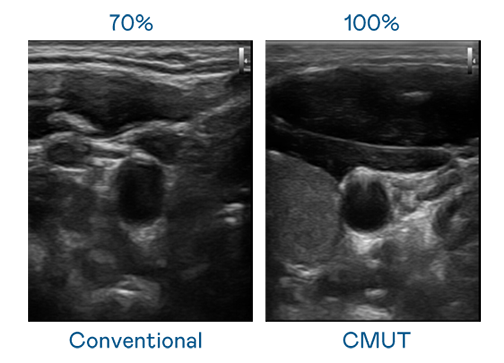

CMUT 技術是一種用電容式微機電元件來產生超音波訊號的技術。與傳統 PZT 壓電式技術相比,CMUT 頻寬增加 30%,更寬頻的超音波訊號讓影像解析度大幅提升,是實現高影像品質醫療超音波掃描、促進精準醫療發展的關鍵技術。

超音波影像的解析度高低,首先取決於探頭能發出的訊號頻寬。vinbet浩博 CMUT 可提供高清晰的超音波訊號,提供高頻寬、高靈敏度、影像紋理細節更高的超音波影像,協助醫護人員縮短影像判讀時間及利用精準的醫療影像進行診斷。